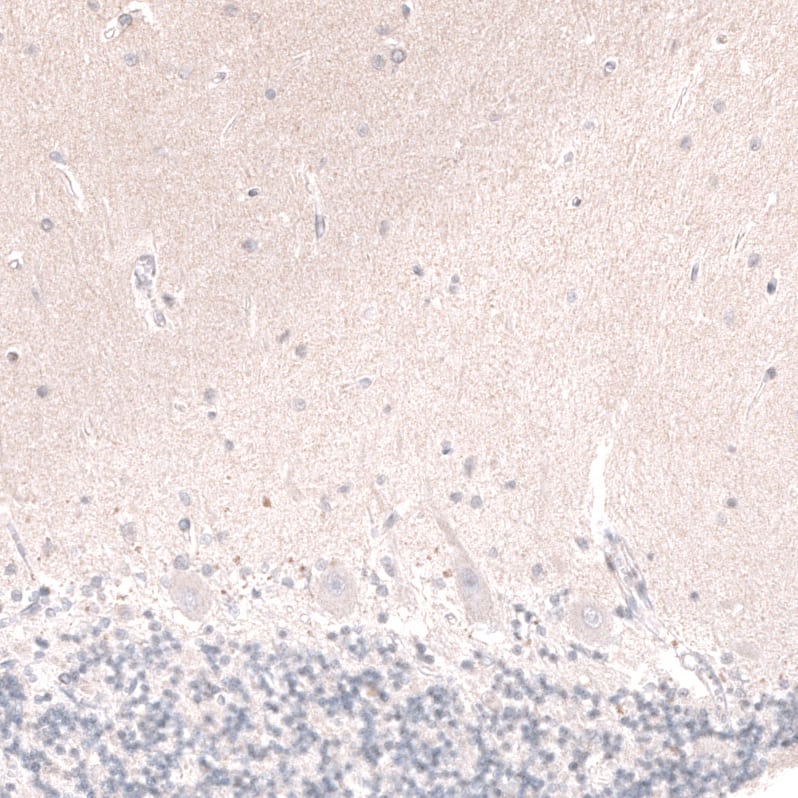

Staining of human cerebellum shows no positivity in Purkinje cells as expected.